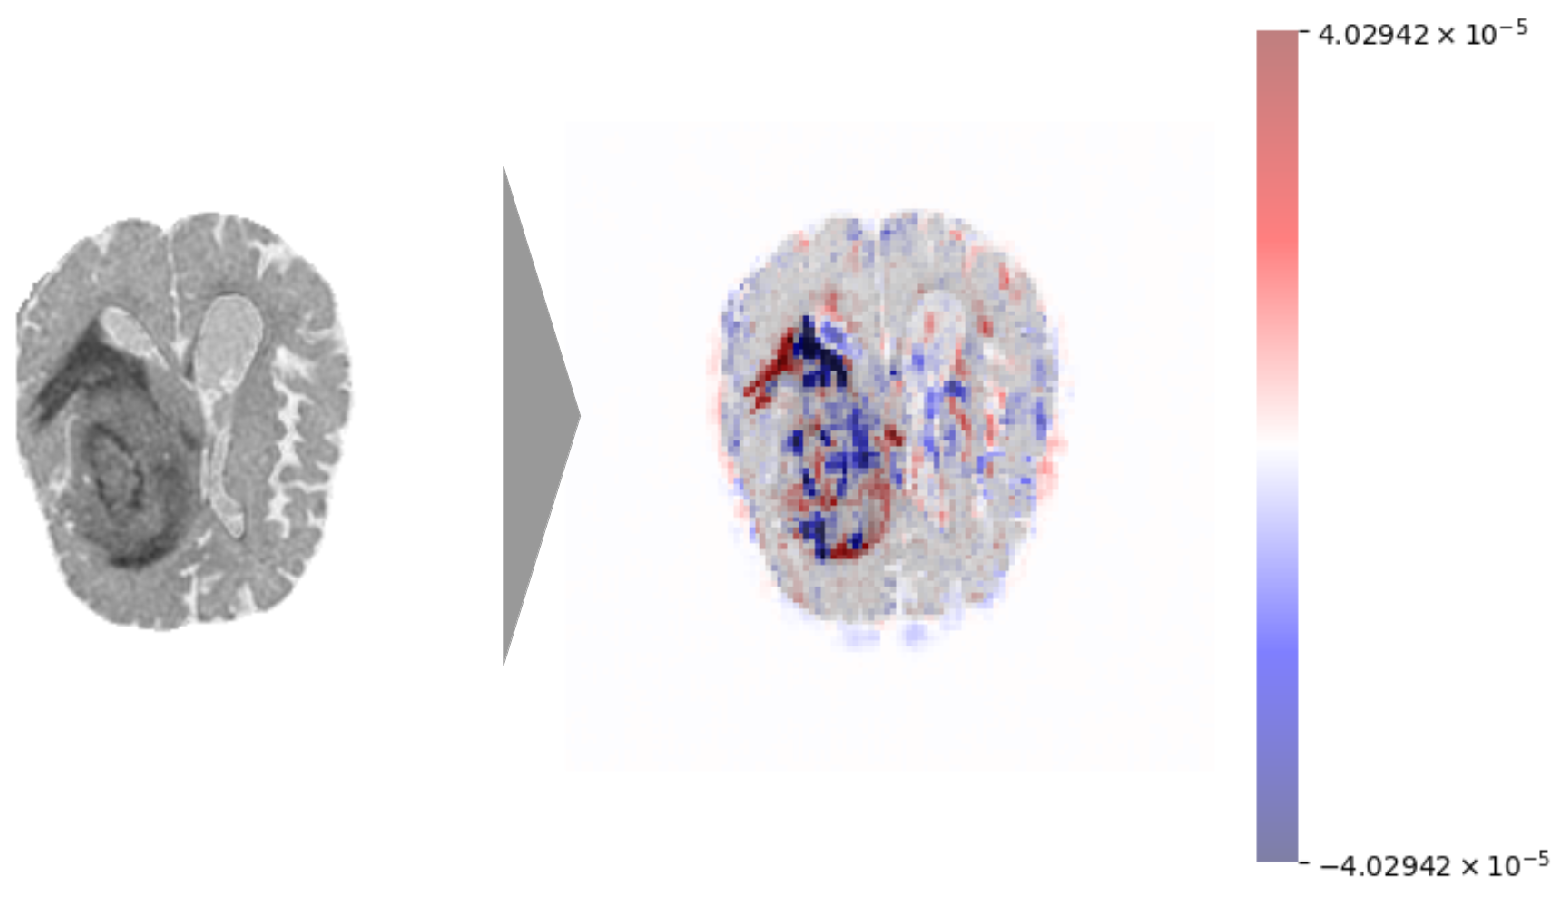

2.1. Data Pre-Processing

2.3. Explainability